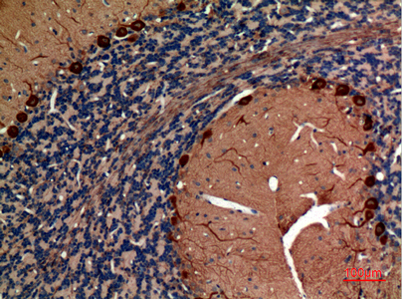

| Dilutions: | Western Blot: 1/500 - 1/2000. IHC-p: 1:100-300 ELISA: 1/20000. Not yet tested in other applications. |

| Background: | This gene encodes a member of the class I fructose-biphosphate aldolase gene family. Expressed specifically in the hippocampus and Purkinje cells of the brain, the encoded protein is a glycolytic enzyme that catalyzes the reversible aldol cleavage of fructose-1,6-biphosphate and fructose 1-phosphate to dihydroxyacetone phosphate and either glyceraldehyde-3-phosphate or glyceraldehyde, respectively. [provided by RefSeq, Jul 2008], |